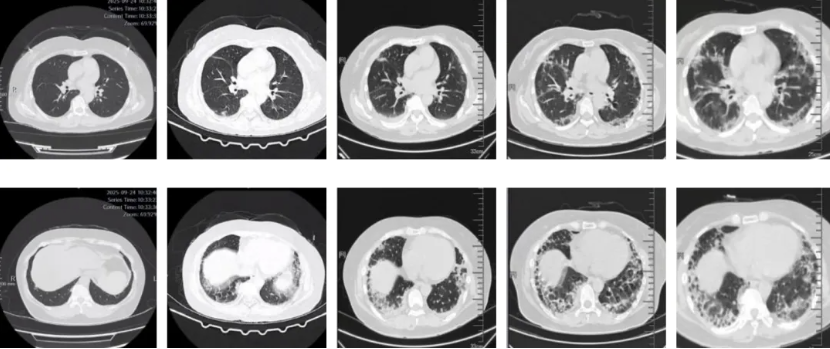

图:(从左至右)9-24、10-7、10-14、10-23、10-27

但很快患者的病情升级,影像学进展,氧和指数持续降低。入院后完善检查,患者血气分析提示低氧血症,复查胸部CT见双肺胸膜下病变范围进一步增大,部分呈间质样改变,结合患者“皮疹+肌损害+间质性肺病”的疾病模式,我们仍然考虑CTD-ILD,重点考虑肌炎相关的间质性肺炎,为进一步明确诊断,予外送肌炎特异性抗体谱25项抗体检测,在等待结果汇报的过程中患者干咳气喘症状逐渐加重,血气分析提示氧和指数逐渐降低。

经治疗后,患者氧合改善不明显,转入RICU,更换HFNC支持,后续病情持续进展,经气管插管呼吸机辅助通气亦不能维持,需ECMO支持,最终因呼吸衰竭死亡。

抗MDA5抗体阳性皮肌炎相关ILD可能在HRCT上表现为严重的OP,直接导致弥漫性肺泡损伤,而无慢性肺部改变。下肺外侧带或沿支气管血管束分布的实变或磨玻璃影(ground glass opacities, GGO)是抗MDA5抗体阳性皮肌炎HRCT上的特征性表现,且与短期预后相关。通过动态监测HRCT的变化,对抗MDA5抗体阳性皮肌炎出现RP-ILD的早期诊断具有重要价值。HRCT显示进展为RP-ILD的特征性表现为在短期内从胸膜下或(和)小叶周围斑片状影迅速进展为广泛的实变影。